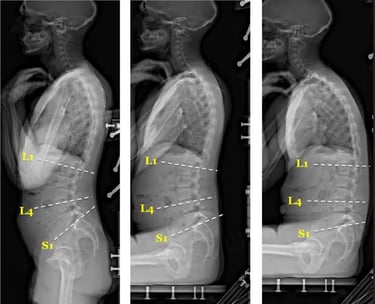

Chiropractic and Physical Therapy Techniques